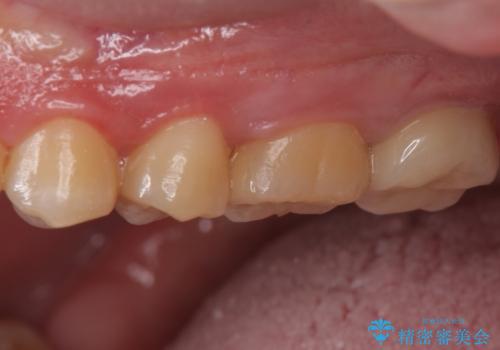

- 奥歯に穴が開いた気がするとのことで来院。

検査の結果、左上の奥歯に大きな虫歯があることが確認できました。

患者様のご希望もあり、今回はセラミックでの治療となりました。

- 左上6:セラミックインレー/77,000円 左上7:仮歯+ジルコニアクラウン/11,000+110,000円費用は治療当時の料金となります

歯の表面に穴が開くほどの虫歯は歯の中でかなり大きくなっていることが多いです。

虫歯の除去後は適合の良い修復物を入れることで今後の虫歯リスクを減らします。